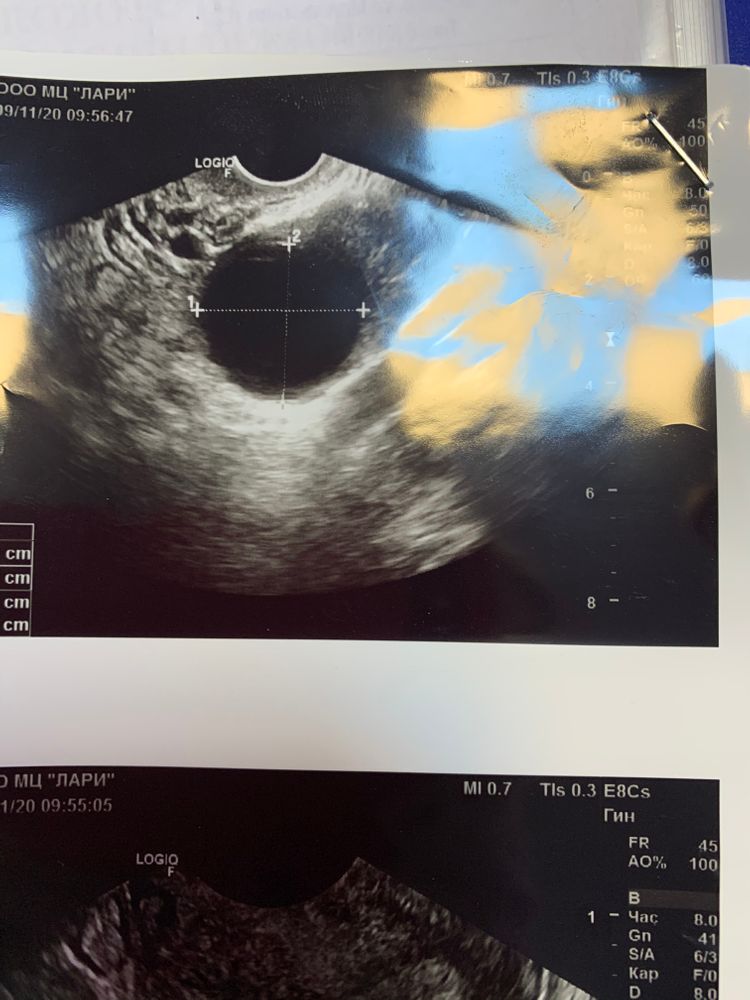

Тест на овуляцию был положительным на 13 дц и ощущения непередаваемые ) пошла на фолликулометрию на 15 дц , она сказала не было овуляции перерастёт в кисту , делаю укол хгч вот узи ..

Дальше иду в другую клинику на 16 дц, там уверенно мне говорят есть киста жт с кровотоком ( даже показала) и жидкость овуляция была день -два назад . Вот фото